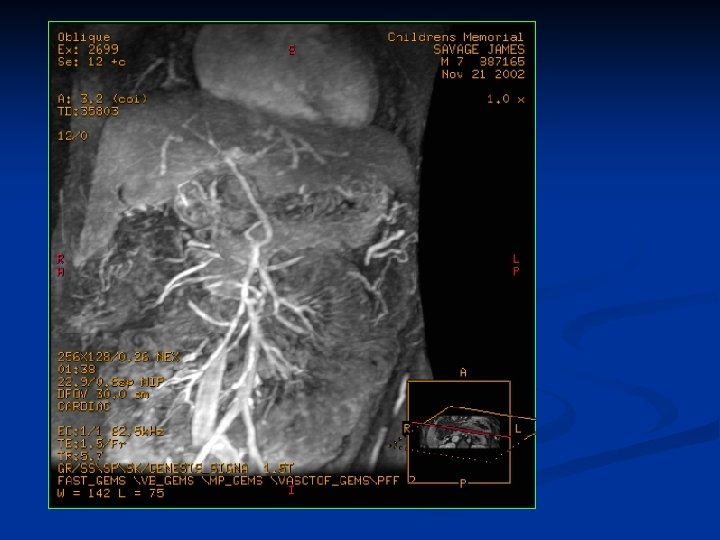

3 -D Tomografia Computadorizada Portografia

Resultados- As veias portais extrahepaticas, foram visualizadas em todos os pacientes pela 3 D- TC Portografia Nenhum desses pacientes mostrou extrahepática obstrução venosa ou transformação cavernomatosa. Todos os pacientes apresentavam uma tortuosa veia portal extrahepática em forma de N, e uma linha podia ser traçada entre as flexuras da veia portal e o hilo hepatico Nenhum paciente tinha história de Onfalite ou Cateterismo da veia umbilical